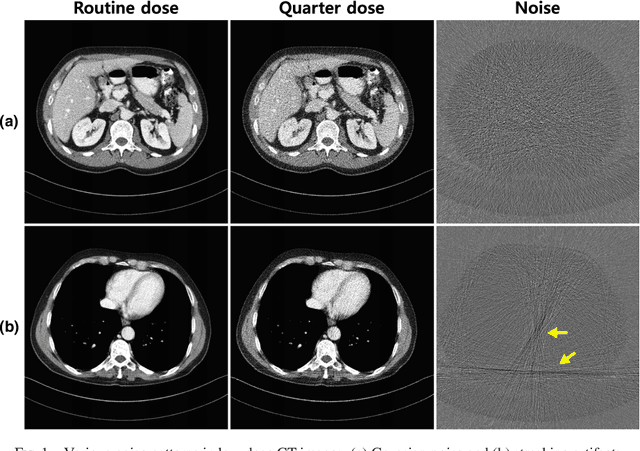

Abstract:Due to the potential risk of inducing cancers, radiation dose of X-ray CT should be reduced for routine patient scanning. However, in low-dose X-ray CT, severe artifacts usually occur due to photon starvation, beamhardening, etc, which decrease the reliability of diagnosis. Thus, high quality reconstruction from low-dose X-ray CT data has become one of the important research topics in CT community. Conventional model-based denoising approaches are, however, computationally very expensive, and image domain denoising approaches hardly deal with CT specific noise patterns. To address these issues, we propose an algorithm using a deep convolutional neural network (CNN), which is applied to wavelet transform coefficients of low-dose CT images. Specifically, by using a directional wavelet transform for extracting directional component of artifacts and exploiting the intra- and inter-band correlations, our deep network can effectively suppress CT specific noises. Moreover, our CNN is designed to have various types of residual learning architecture for faster network training and better denoising. Experimental results confirm that the proposed algorithm effectively removes complex noise patterns of CT images, originated from the reduced X-ray dose. In addition, we show that wavelet domain CNN is efficient in removing the noises from low-dose CT compared to an image domain CNN. Our results were rigorously evaluated by several radiologists and won the second place award in 2016 AAPM Low-Dose CT Grand Challenge. To the best of our knowledge, this work is the first deep learning architecture for low-dose CT reconstruction that has been rigorously evaluated and proven for its efficacy.

Abstract:Model based iterative reconstruction (MBIR) algorithms for low-dose X-ray CT are computationally complex because of the repeated use of the forward and backward projection. Inspired by this success of deep learning in computer vision applications, we recently proposed a deep convolutional neural network (CNN) for low-dose X-ray CT and won the second place in 2016 AAPM Low-Dose CT Grand Challenge. However, some of the texture are not fully recovered, which was unfamiliar to some radiologists. To cope with this problem, here we propose a direct residual learning approach on directional wavelet domain to solve this problem and to improve the performance against previous work. In particular, the new network estimates the noise of each input wavelet transform, and then the de-noised wavelet coefficients are obtained by subtracting the noise from the input wavelet transform bands. The experimental results confirm that the proposed network has significantly improved performance, preserving the detail texture of the original images.